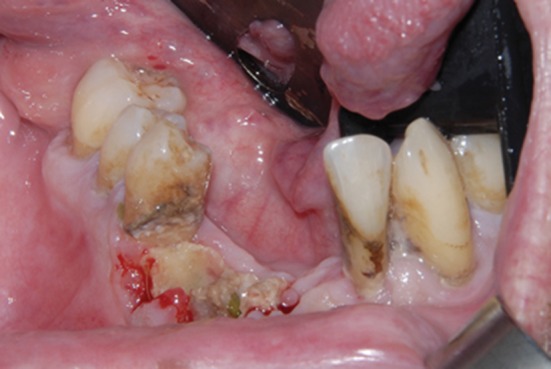

Fig. 2.

Clinical picture of BIONJ.

Image Credits: Mayo Clinic